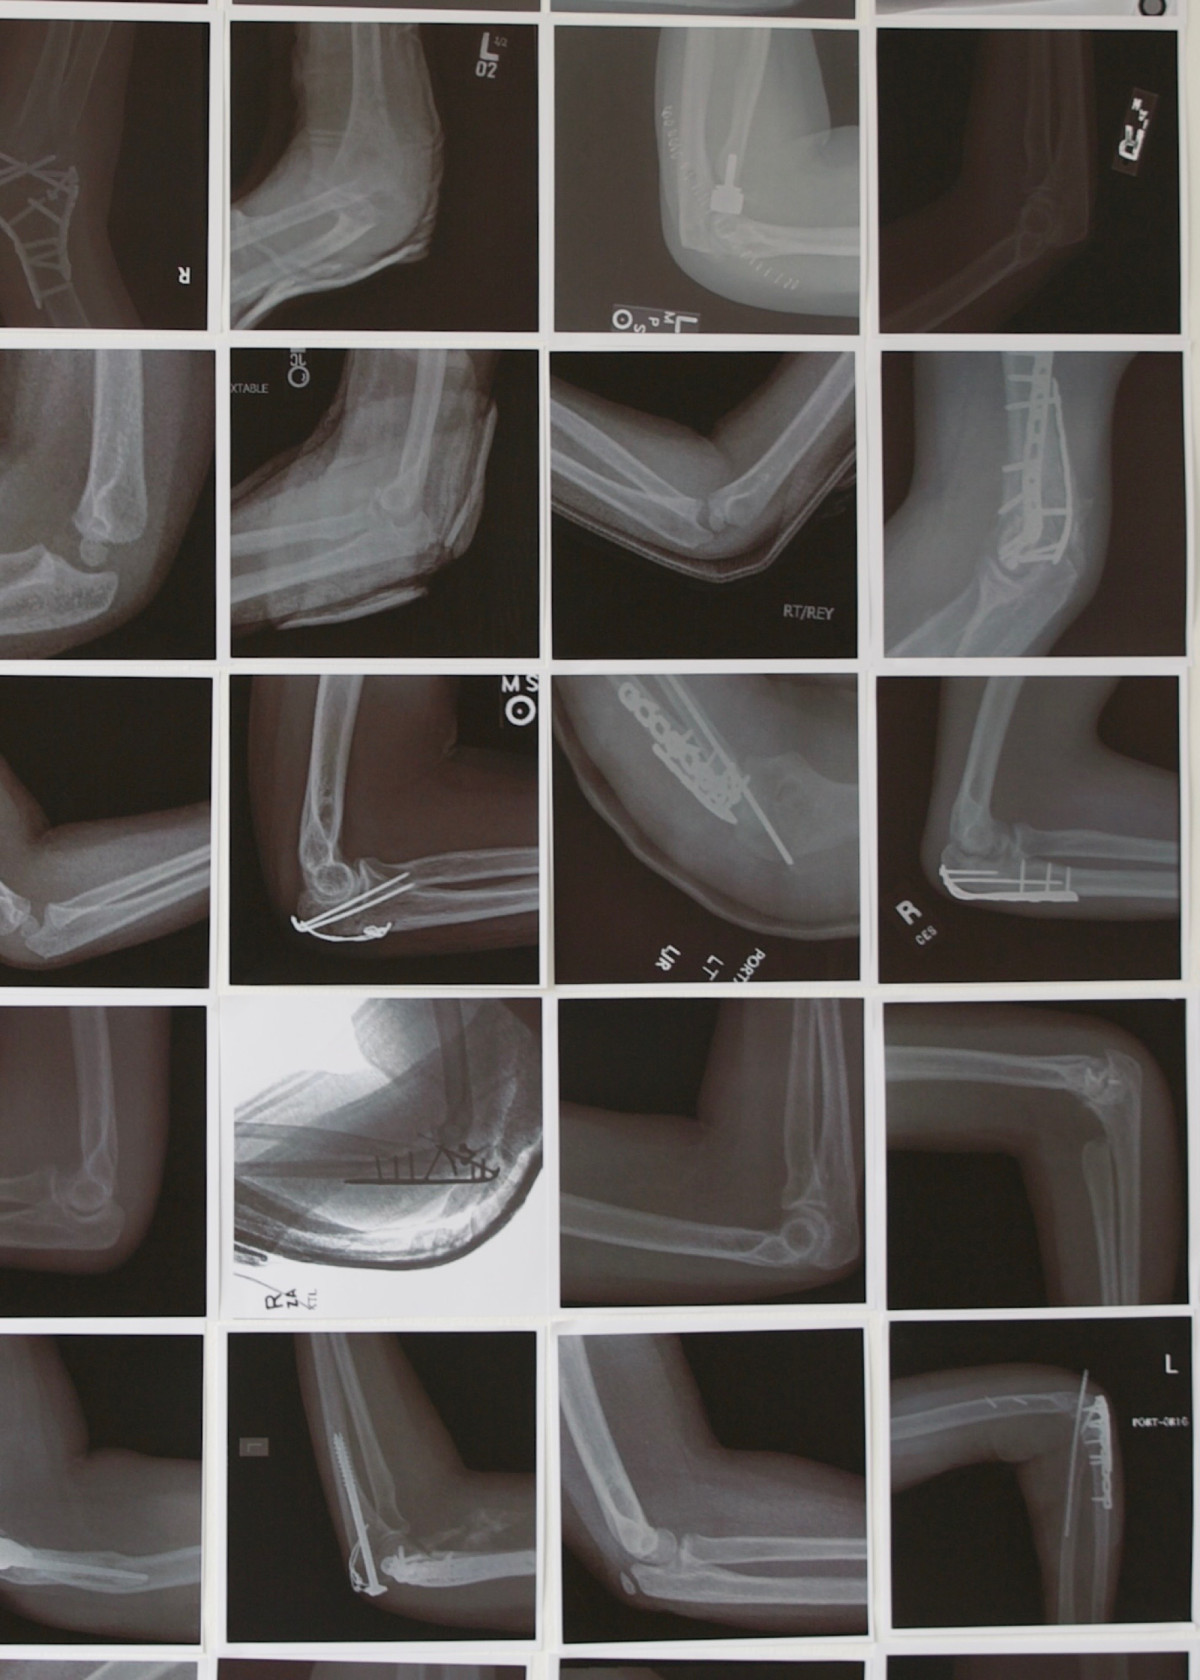

Die Arbeit Cubiti zeigt 567 Röntgenbilder unterschiedlicher Ellenbogen. Unabhängig von der gesundheitlichen Verfassung geben die Bilder keine Information über das Alter, die Herkunft oder das Geschlecht des Menschen, zu dem der Ellenbogen gehört. Die Bilder beschäftigen sich mit dem Teil unseres Körpers, der nicht offensichtlich ist und dem wir alltäglich kaum Beachtung schenken.

The work Cubiti shows 567 x-ray images of different elbows. Regardless of the patient's health, the images provide no information about the age, origin, or gender of the person to whom the elbow belongs. The images focus on the part of our body that is not obvious and to which we pay little to no attention in our daily lives.